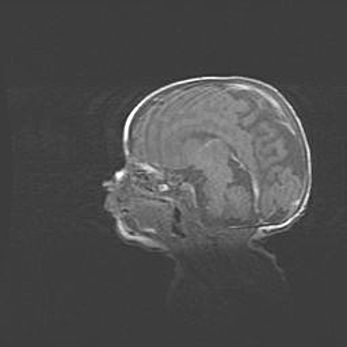

Лейкомаляция с кистозно-глиозной дегенерацией головного мозга.

Возраст: 2 месяца 25 дней

Вес: 6400 г

Окружность головы: 40 см

Срок гестации: 41 неделя

Лейкомаляцию относят к ишемически-гипоксическим повреждениям головного мозга, диагностируемым у новорожденных. При лейкомаляции в головном мозге обнаруживают очаги некроза, возникшие после тяжелой гипоксии и нарушения кровотока. В процессе морфогенеза очаги проходят три стадии: 1) развития некроза, 2) резорбции и 3) формирования глиозного рубца или кисты. Перивентрикулярная лейкомаляция (ПЛ) встречается примерно в 12% случаев среди новорожденных, обычно – у недоношенных детей, причем, частота ее зависит от массы, с которой младенец появился на свет. Наибольшее число малышей страдает лейкомаляцией, если масса при рождении 1500-2500 г.